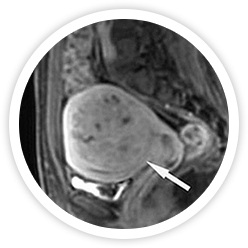

• 시술전 사진 시술 전

하이푸 시술 전에 MRI 조영증강영상에 점막하근종이 보임